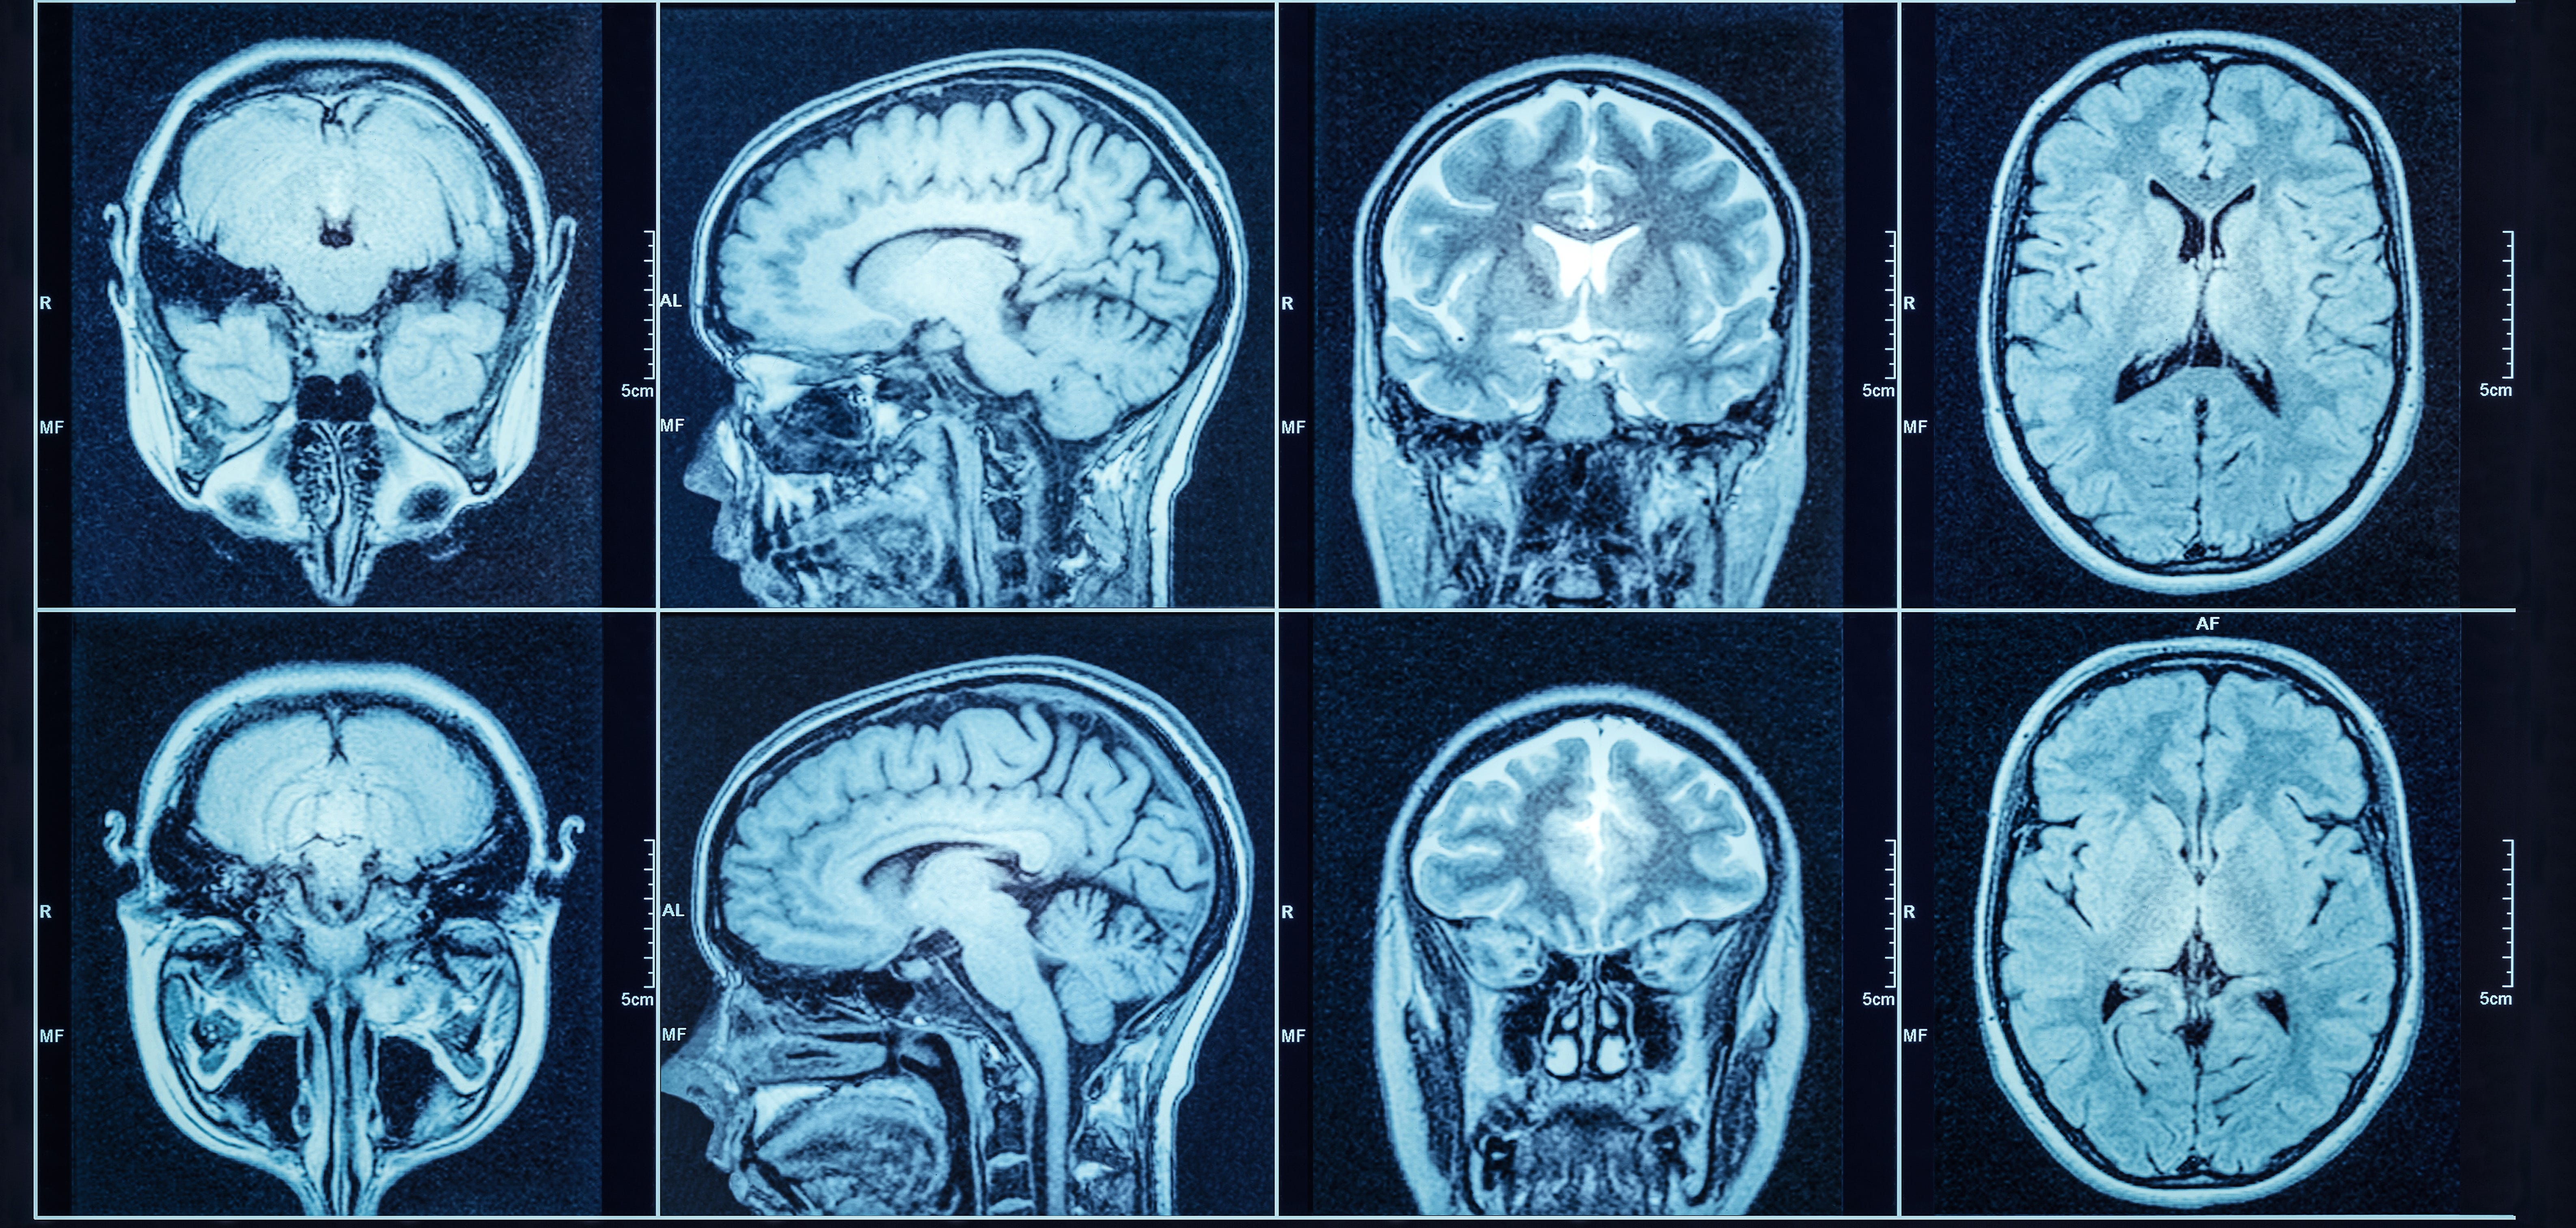

Many "vegetative" patients are conscious and responsive

"Cognitive-motor dissociation" complicates the prognosis of unresponsive patients

Patients who become persistently encephalopathic after the resolution of severe illness (e.g., brain injury due to trauma, ischemic or hemorrhagic stroke) enter a liminal state of existence while those around them decide their fate.

It’s been widely assumed that people with no response to verbal commands experience are effectively cut off from the world …